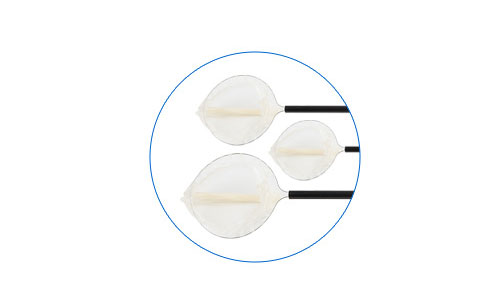

● 不同张口大小和容量,适用不同标本大小

多种规格可选 不同张口大小和容量,适用不同标本大小